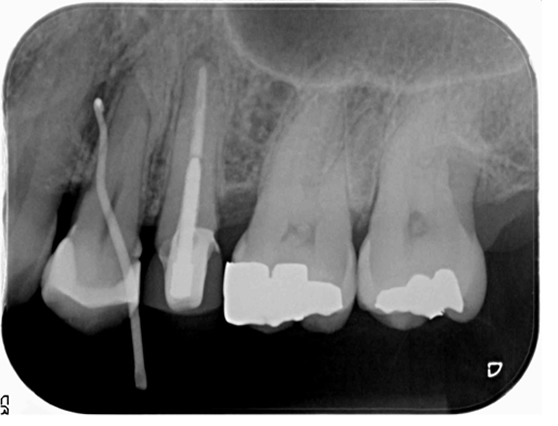

左上の5番が再治療しても歯茎の腫れが直らないとのことでしたが、当院での審査の結果、原因は左上4番(隣の歯)の神経が死んでしまっている事でした。左上4番の根幹治療を行い、その後症状は消失し経過は良好です。

| 治療前 | ![]() |